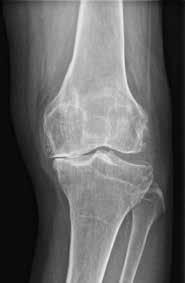

(Top, from left) X-ray images show a normal knee; unicompartment OA with some wearing on inner side of knee; and post-partial knee replacement.

(Bottom, from left)

Tricompartment OA with severe damage to both knees; and post-total knee replacement.

Not all bad knees need a total replacement of the joint. It is only when joint damage is very severe or complex that a total knee replacement (TKR) is likely. Otherwise, partial knee replacement (PKR) or knee preservation (KP) are options for those whose knees are less damaged.

Knee pain can be due to diseases like gout and rheumatoid arthritis, but is most often due to osteoarthritis (OA), where the protective cartilage that cushions the joints is worn down over time. OA is a significant health concern due to its impact on mobility and quality of life. Typically a disease of the elderly, OA is increasingly affecting younger

patients amid a rise in popularity of vigorous sporting activities.

TKR is typically recommended for patients with OA affecting the entire knee joint, significant deformity, or extensive damage to the three areas, or compartments, of the knee. It may also be recommended for patients with inflammatory arthritis, post-traumatic arthritis, or other conditions causing severe knee pain and functional impairment.